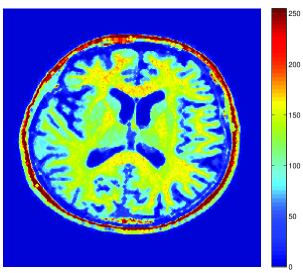

Here, is a uniform blur with . A () medical image shown in Fig. 5(a) is degraded by and corrupted by a Poisson noise following the model described in the previous section for various intensity levels. The degraded image is displayed in Fig. 5(b) when .

To evaluate the performance of our algorithm we use the Signal to Noise Ratio defined in Section 5.3.2. Tab. 2 shows the values of the obtained for different values of and . As predicted by Proposition 5.4(v), beyond some value of , which is dependent of , the optimal value is found. We also compare our results with those provided by two different approaches. The first one is the regularized Expectation Maximization (EM) approach (also sometimes called SMART) [10, 31] where the Poisson anti-likelihood penalized by a term proportional to the Kullback-Leibler divergence between the desired solution and a reference image is minimized. Its weighting factor has been adjusted manually so as to maximize the and, the reference image is a constant image whose pixel values has been set to the mean value of the degraded image. The other approach is the method based on the Anscombe transform proposed in [24] and discussed in Remark 5.6. For fair comparisons, the method here employs the same orthonormal wavelet representation, the same functions as ours and the same constraint set . It can be observed that the approach we propose gives good results. However, for high intensity levels (), the method based on the Anscombe transform performs equally well in terms of SNR. The restored images are shown in Fig. 5, when and after 3000 iterations. In spite of an important degradation of the original image, it can be seen that our approach is able to recover the main features in the image. It can also be noticed that the image restored by the two methods exhibit different visual characteristics.

![]() |

| (a) | |

| (b) | (c) |

| (d) | (e) |